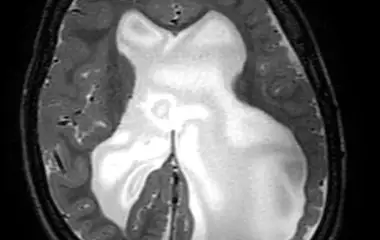

Hydrocephalus (Wasserkopf)

Ein Hydrocephalus entsteht durch eine Störung des Hirnwasserflusses oder der Aufnahme des Hirnwassers ins Körpersystem. Dies kann zu einer Vergrößerung der Hirnkammern und einem erhöhten Druck im Kopf führen. Typische Symptome sind ein schnell wachsender Kopfumfang, Kopfschmerzen oder Entwicklungsverzögerungen. Die Behandlung erfolgt meist operativ durch eine Ableitung des Hirnwassers, z. B. mit einem Shunt-System oder einer endoskopischen Technik.